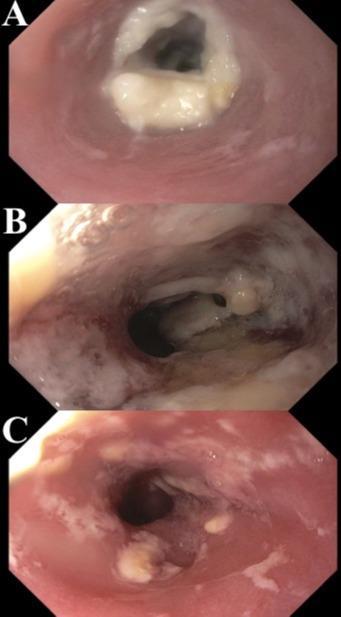

YOU SHALL NOT PASS: RARE DUODENAL BULB ADENOCARCINOMA CAUSING GASTRIC OUTLET OBSTRUCTION

50

Randy Leibowitz1 , Alexander Maraveyas1, Frederick Rozenshteyn1, Tina Park1

1Mount Sinai Morningside-West Hospitals, Icahn School of Medicine at Mount Sinai, New York, NY, United States Presented at the American College of Gastroenterology (ACG) Annual Meeting that was held in Charlotte, North Carolina, United States from October 21-26, 2022.